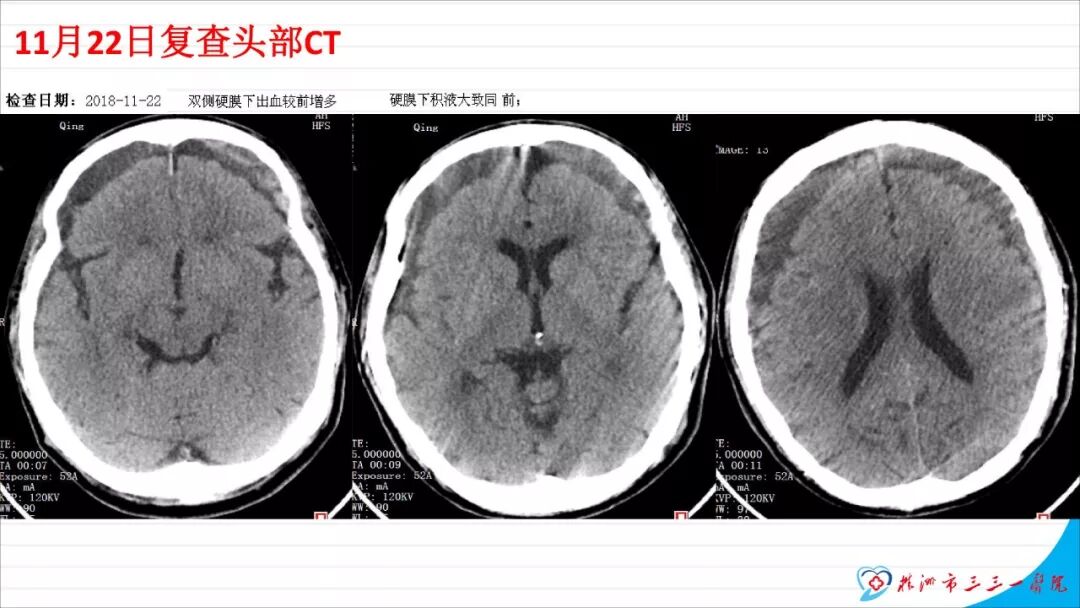

本文以“慢性硬膜下血肿自然演变一例”为题,恰当!因为此例患者系从急性硬膜下血肿自然演变而来。只是长期口服他汀没有起到预防作用。本例患者与其说是阿托伐他汀治疗慢性硬膜下血肿无效,还不如说是阿托伐他汀不能阻止急性硬膜下血肿向慢性硬膜下血肿演变的过程,当然,后续急性血肿变成慢性后,阿托伐他汀似乎也没有发挥治疗作用。需要指出的是,单药阿托伐他汀治疗急性硬膜下血肿并无成功病例报道,但是,本例报道还告诉我们,它还不能阻止急性硬膜下血肿向慢性血肿演变,值得关注。 谈到阿托伐他汀治疗慢性硬膜下血肿,我们是始创者。为此,看到作者似乎有点抱怨的情绪,我得做些解释。我们ATOCH试验,验证的是阿托伐他汀治疗慢性硬膜下血肿比安慰剂能更有效促进血肿吸收,没有发现也没有努力去验证阿托伐他汀治疗慢性硬膜下血肿100%有效,因此发生治疗无效很正常。 保守治疗的始作俑者是英国人,他们1962年就提出地塞米松治疗慢性硬膜下血肿。但是,迄今为止,无论是英国人提出的地塞米松、美国人提出的氨甲环酸或血管紧张素转换酶抑制剂,还是德国人提出的塞來西布,日本人提出的汉药,国内许多单位自行研究提出的血府逐瘀丸,作者单位的“传统”方法红花注射液治疗慢性硬膜下血肿都没有经历严格随机双盲安慰剂对照研究,也从未被大宗病例报道证实过有效。由于未被RCT(随机对照临床试验)证实过,加上一部分慢性硬膜下血肿不必治疗也可以自我吸收(这在我们ATOCH里的安慰剂组中已经观察到,但我们发表论著时没有刻意提出这一点而已),除他汀疗法之外的药物疗法被怀疑是否真具有疗效就顺理成章了。这也是我们的阿托伐他汀治疗慢性硬膜下血肿在保守治疗药物队伍中“一骑绝尘”的理由。后续西南医科大学和香港中文大学还均报道使用阿托伐他汀可以预防慢性硬膜下血肿术后复发。而且,除了有RCT结果支撑其有效性外,安全性明显优于上述各个西药又不像中药或汉药那么含糊,也使得阿托伐他汀成为目前保守治疗慢性硬膜下血肿应用最多的药物。 但毫无疑问,实践中确实屡屡有发现效果不佳的病例。为什么会这样呢?可能有2个理由: 1、确实存在一部分对他汀治疗反应不佳的患者。我们的ATOCH中,阿托伐他汀试验组就有11例患者因无效转去接受手术(对照组则多达23例); 2、ATOCH试验长达8周,有些患者家属和医生都没有耐心等待8周。也就是说,没有等到药物作用显现就转保守治疗为手术治疗。在同样状况下,即使作为发明者,我也不敢“阻扰”患者转手术治疗,因为这意味着风险转嫁。而这种“保守治疗未到时间”(这样提可能不严谨,因为没有规定时间,只有经验时间)就转手术治疗,会增加阿托伐他汀治疗慢性硬膜下血肿的“无效率”。 有鉴于此,我们团队在张建宁教授指导下,从2014年就开始优化阿托伐他汀疗法,本人以此优化的独门方法就治愈了多达200余例各种慢性硬膜下血肿患者。最近,有上海同行私下告诉我,他用类似我的优化方法保守治疗慢性硬膜下血肿多例,还没有失败过。我跟他开玩笑:“那是你治疗的病例还不够多。”实际这不是开玩笑,因为本人有失败经验。目前,我们团队正积极推进ATOCHII试验,就是要证明我们的优化疗法更加有效,期待奉献给世界一个更加好用的治疗慢性硬膜下血肿新方法。 最后需要特别指出的是,慢性硬膜下血肿与急性硬膜下血肿和亚急性硬膜下血肿并非一定有如父如子的“传承”关系。实践中,绝大多数患者都没有急性硬膜下血肿过程,尤其是老年患者第一次查影像学多数就可以确诊慢性硬膜下血肿了,患者之前并没有经历急性硬膜下血肿这种剧烈损伤过程。还有,脑转移癌可以发生类似慢性硬膜下血肿的血肿性病变,先天性蛛网膜囊肿、脑池囊肿术后常见并发症就包括硬膜下血肿。笔者诊疗慢性硬膜下血肿接近300多例,还见过教科书和个案报道没有记载的各种非脑外伤相关慢性硬膜下血肿的病例。相比于脑外伤引起的急性和亚急性硬膜下血肿,慢性硬膜下血肿是处理简单且病情稍显轻微的疾病,但其发生机制却远比急性和亚急性硬膜下血肿更为复杂,值得进一步深入研究。 江荣才 教授 副主任兼NICU主任 天津医科大学总医院神经外科![]()